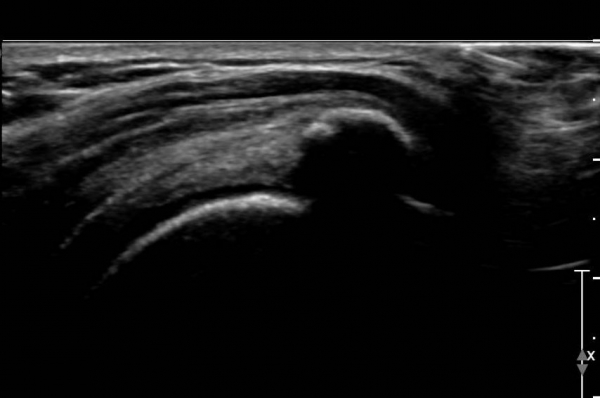

ÃÊÀ½ÆÄ °Ë»ç :  ¿À±¸µ¹±â °ßºÀÀδë Á¾´Ü¸é°Ë»ç¿¡¼­ ÀÎ´ë ½ÉÃþ¿¡ ¼ö¾×Àú·ù°¡ °üÂûµÇ´Âµ¥(»çÁø 1) ÀÌ °ÍÀº

¸¸¼ºÀûÀÎ Ãæµ¹ÁõÈıºÀ» ¾Ï½ÃÇÑ´Ù.

°ß°©ÇÏ±Ù°Ç Á¾´Ü¸é°Ë»ç(»çÁø 2)¿Í ȸ´Ü¸é°Ë»ç(»çÁø 2)¿¡¼­ ÈĹæÀ½¿µÀ» º¸ÀÌ´Â °í¿¡ÄÚ ¼®È¸°¡

°üÂûµÈ´Ù. Åë»óÀûÀÎ °ß°©ÇÏ±Ù°Ç Á¾´Ü¸é°Ë»ç¿¡¼­´Â °ß°©ÇÏ±Ù°Ç »óºÎ ¼®È¸È­·Î º¸ÀÌÁö¸¸ Ⱦ´Ü¸é°Ë»ç·Î

º¼ ¶§ °ß°©ÇÏ±Ù°Ç ÇϺο¡ ¹ß»ýÇÑ ¼®È¸ÀÓÀ» ¾Ë ¼ö ÀÖ´Ù.